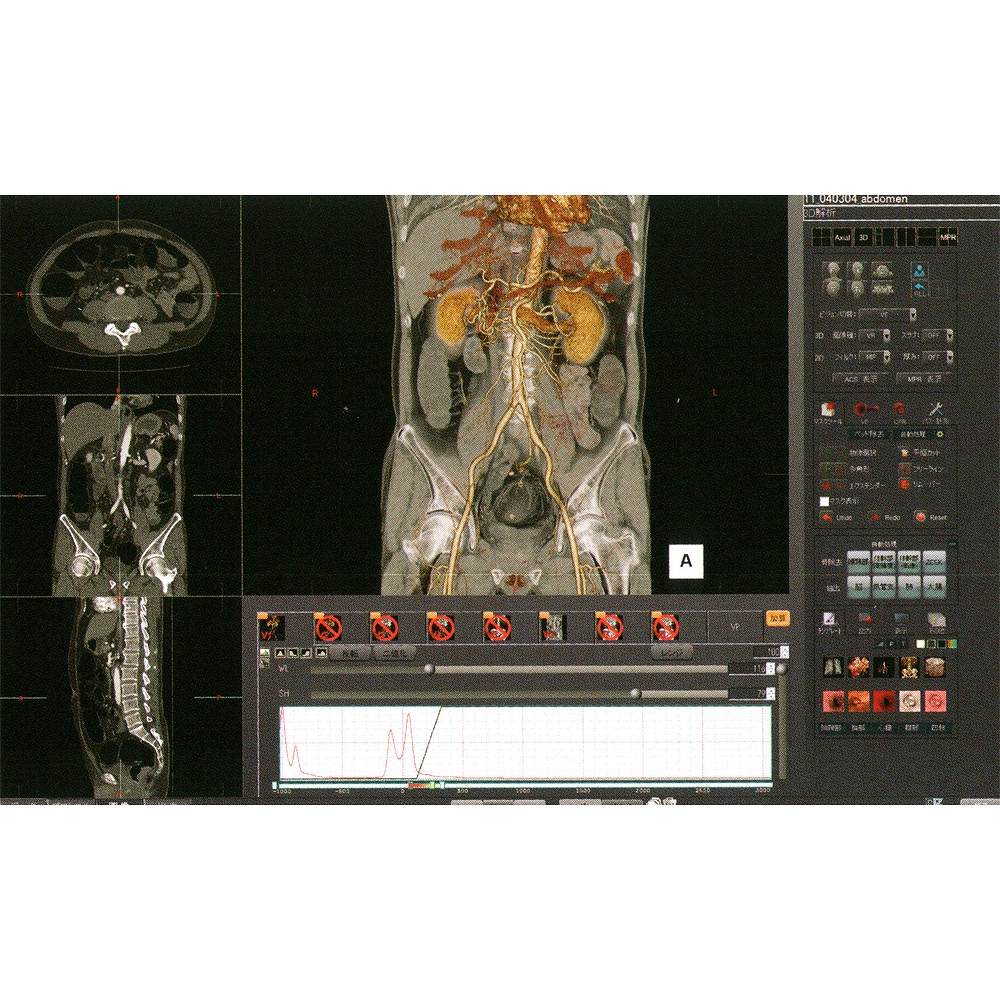

正規代理店 医療用3Dワークステーションで学ぶ 脳神経外科手術戦略 健康・医学

正規代理店 医療用3Dワークステーションで学ぶ 脳神経外科手術戦略 健康・医学

医療用3Dワークステーションで学ぶ 脳神経外科手術戦略。医療用3Dワークステーションで学ぶ 脳神経外科手術戦略。医療用3Dワークステーションで学ぶ 脳神経外科手術戦略。・新品を裁断しました。脳神経外科診療プラクティス 5 裁断済み。3D医用画像ワークステーション ziostation2 | 映像情報Medical。\r(「やや傷や汚れあり」にしております)\r\r・書き込みなし\r\r中古品であること、ご理解の上、ご購入ご検討ください。\r\r「医療用3Dワークステーションで学ぶ 脳神経外科手術戦略シミュレーション」\r井川 房夫 / 中冨 浩文 / 山田 茂樹\r定価: ¥ 10000\r\r#井川房夫 #井川_房夫 #中冨浩文 #中冨_浩文 #山田茂樹 #山田_茂樹 #本 #自然/医療・薬学・健康\r「医療用3Dワークステーションで学ぶ 脳神経外科手術戦略シミュレーション」\r井川 房夫 / 中冨 浩文 / 山田 茂樹\r定価: ¥ 10000\r\r#井川房夫 #井川_房夫 #中冨浩文 #中冨_浩文 #山田茂樹 #山田_茂樹 #本 #自然/医療・薬学・健康